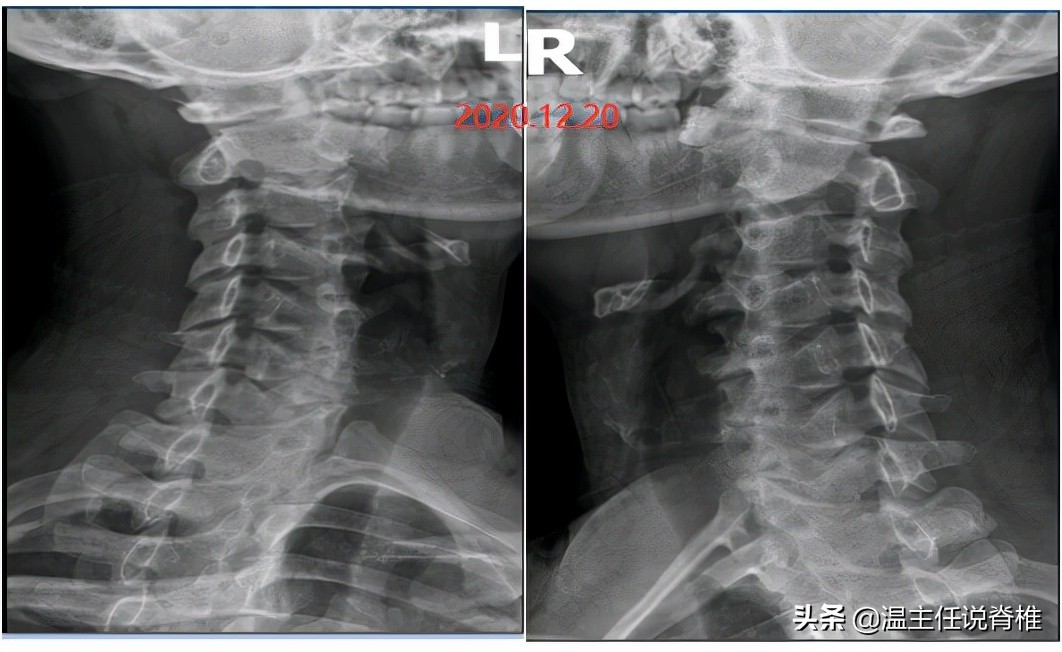

于是在去年的12月份,该病人来到龙脊康就诊,我们结合体格检查和X光片,发现他有颈椎生理曲度变直,项韧带钙化,颈2/3棘突偏右,颈5/6椎间隙变窄,颈7到胸3棘突偏右。因此诊断病人为脊椎病(混合型颈椎病),当时以为他只是单纯颈部酸痛,加上并没有手麻的情况,神经反射检查未见异常;所以采用了常规手法、正骨复位、中医理疗等治疗。

下图是我对他前后8个月来就诊时,进行两张颈椎双斜位片的对比,病人颈3/4椎间孔已经明显变窄。